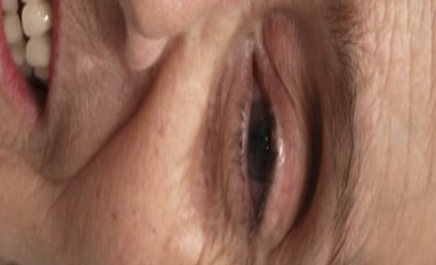

Paciente que acude por fracaso de los dientes del maxilar superior por enfermedad periodontal

TRATAMIENTO en una sola fase: exodoncias, colocación de 8 implantes y dientes fijos en el día (carga inmediata). Prótesis definitiva de metal-porcelana

Prótesis fija maxilar sobre implantes y rehabilitación dentosoportada mandibular

Paciente que acude por fracaso de dientes de maxilar superior y rehabilitacion dento soportada de la mandíbula.

En una sola fase realizamos las exodoncias, colocación de 6 implantes y dientes fijos en el día (carga inmediata). Prótesis definitiva de metal-porcelana.